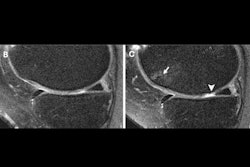

A knee joint of a patient on imaging shows (A) severe cartilage defects and (B) an intact knee joint. Images and caption courtesy of RSNA.The team found significant ties between corticosteroid injection and postinjection progression of whole-organ MRI scores over two years for the knee overall, lateral meniscus, lateral cartilage, and medial cartilage.

However, the study authors found no such links between either injection type and pain progression, as well as progression of MRI scores over the two years prior to injection.